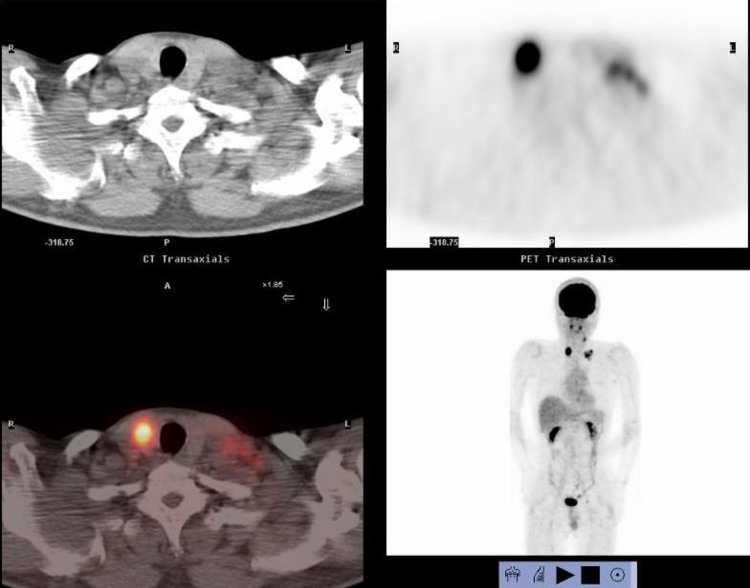

Fig. 3.

Positron emission tomography showed that increased standardized uptake values (SUV) of 28.0 and 7.0 were observed in the thyroid gland tumor and left cervical region

A 53-year-old male presented with a chief complaint of a bloody stool. Colonoscopy showed circumferential ulcer in cecum, and abdominal computed tomography (CT) showed wall thickening in cecum and enlarged lymph nodes. No metastasis was revealed in the liver and lungs. Radiographic contrast enema revealed apple-core-sign in cecum. Mild anemia was shown (Hb 11.2 g/dL), and carcino-embryonic antigen (CEA = 5.2) and carbohydrate antigen 19-9 (CA19-9 = 308.9) were elevated in blood examination. The preoperative diagnosis was colon cancer, C, SS, N2, H0, P0, M0 Stage IIIb by the Japanese Classification of the Colorectal Carcinoma (JCCC) [1]. Right colectomy with D3 lymph node dissection was performed (Fig. 1). Histological examination showed colon cancer, C, type 2, 45 × 30 mm, 1/2 circ, tub2 > tub1 > por1 > por2, SE, int, ly2, v1, N3 [No201(10/13), 211(0/4), 202(1/2), 203(1/3)], H0, P0, M0, PM0, DM0, RM0, Stage IIIb by JCCC. After the operation, the patient received chemotherapy with Capecitabine regimen (starting dose: Xeloda® 4200 mg/body orally on day1–14, every 3 weeks). During 3 cycles of Capecitabine regimen, due to the onset of icterus (Grade2), we managed to continue Capecitabine regimen with the extension of interval period and dose reduction. But after 6 cycles of Capecitabine regimen, icterus was exacerbated. The chemotherapy was aborted. After 1 year later, CT detected swelling of Virchow’s lymph node and tumor in the thyroid gland (Fig. 2). Positron emission tomography showed that increased standardized uptake values (SUV) of 28.0 and 7.0 were observed in the thyroid gland tumor and left cervical region (Fig. 3). By fine-needle aspiration cytology, thyroid gland tumor was diagnosed as papillary carcinoma and Virchow’s lymph node was detected adenocarcinoma which was metastasis of cecal cancer. We diagnosed, thyroid papillary carcinoma, T3, N1b, M0, Stage IVa and recurrence of cecal cancer in Virchow’s lymph node. In selecting surgical therapy or chemotherapy, chemotherapy has side effects of icterus due to Capecitabine, there was a possibility that chemotherapy was difficult to continue. In surgical treatment, cervical dissection was possible in the treatment of thyroid papillary carcinoma, and no organ metastasis in the whole clinical course and no other sites of nodal metastasis except Virchow’s node at the time of the recurrence. From these points, we thought that surgical treatment was better than chemotherapy. After informed consent from surgeon and otolaryngologist, the patient wished surgical treatment. Total thyroidectomy and cervical lymph node dissection was performed. Finally histological examination revealed that Virchow’s lymph node was moderately differentiated adenocarcinoma as a metastatic cecal cancer (Fig. 4). After the operation, the patient received chemotherapy with 6 cycles of FOLFOX regimen (5-FU bolus 720 and 4250 mg/body, leucovorin 360 mg/body and oxaliplatin 150 mg/body). And the patient had taken UFT/LV for 30 months. After UFT/LV regimen, the patient selected follow-up without chemotherapy. Now he has no recurrence and keeps his quality of life high. He has been surviving for 80 months since the first operation (Fig. 5).